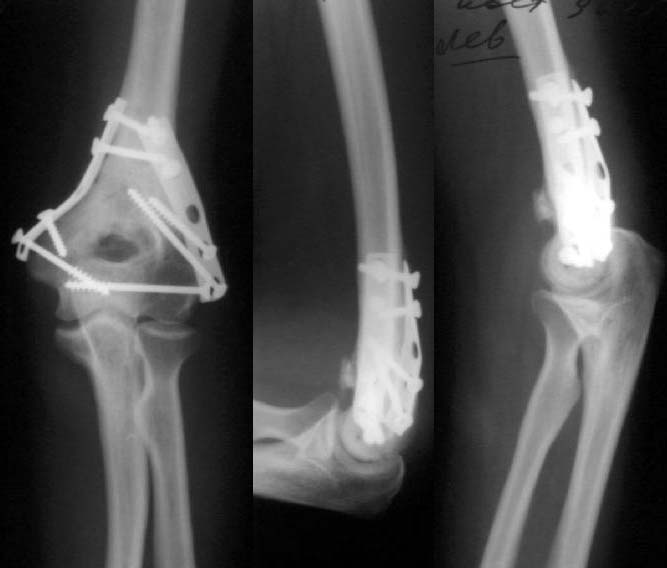

Все же открываться мы не стали. Результаты в приложении. Фронтальный снимок переделаю и пришлю еще раз. Мнения?

Кликните для загрузки файла k5.jpg

9KB (9874 bytes)